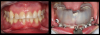

Fig 5. Class 3 fractures with caries of dentin and cementum (nonrestorable)

(left) and guided smile synchronized to extract, place, and

restore 3.5 x 16 mm implants.

Figure 5